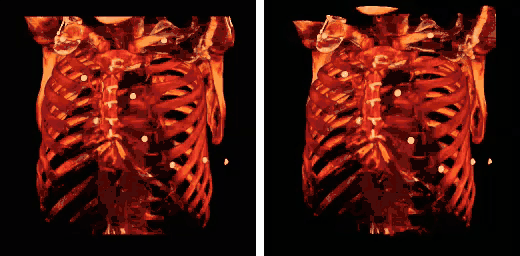

The influence on volume rendering of various shading settings is shown below:

The shading settings used for the above images are as follows:

| Image | Ambient Coefficient | Diffuse Coefficient | Specular Coefficient | Specular Power |

|---|---|---|---|---|

| Top Left | 0.15

|

0.9

0.3

15.0

| Top Middle | 0.75

| Top Right | 0.15

0.1

| Bottom Left | 0.15

1.2

| Bottom Middle | 0.15

1.0

| Bottom Right | 0.15

0.6